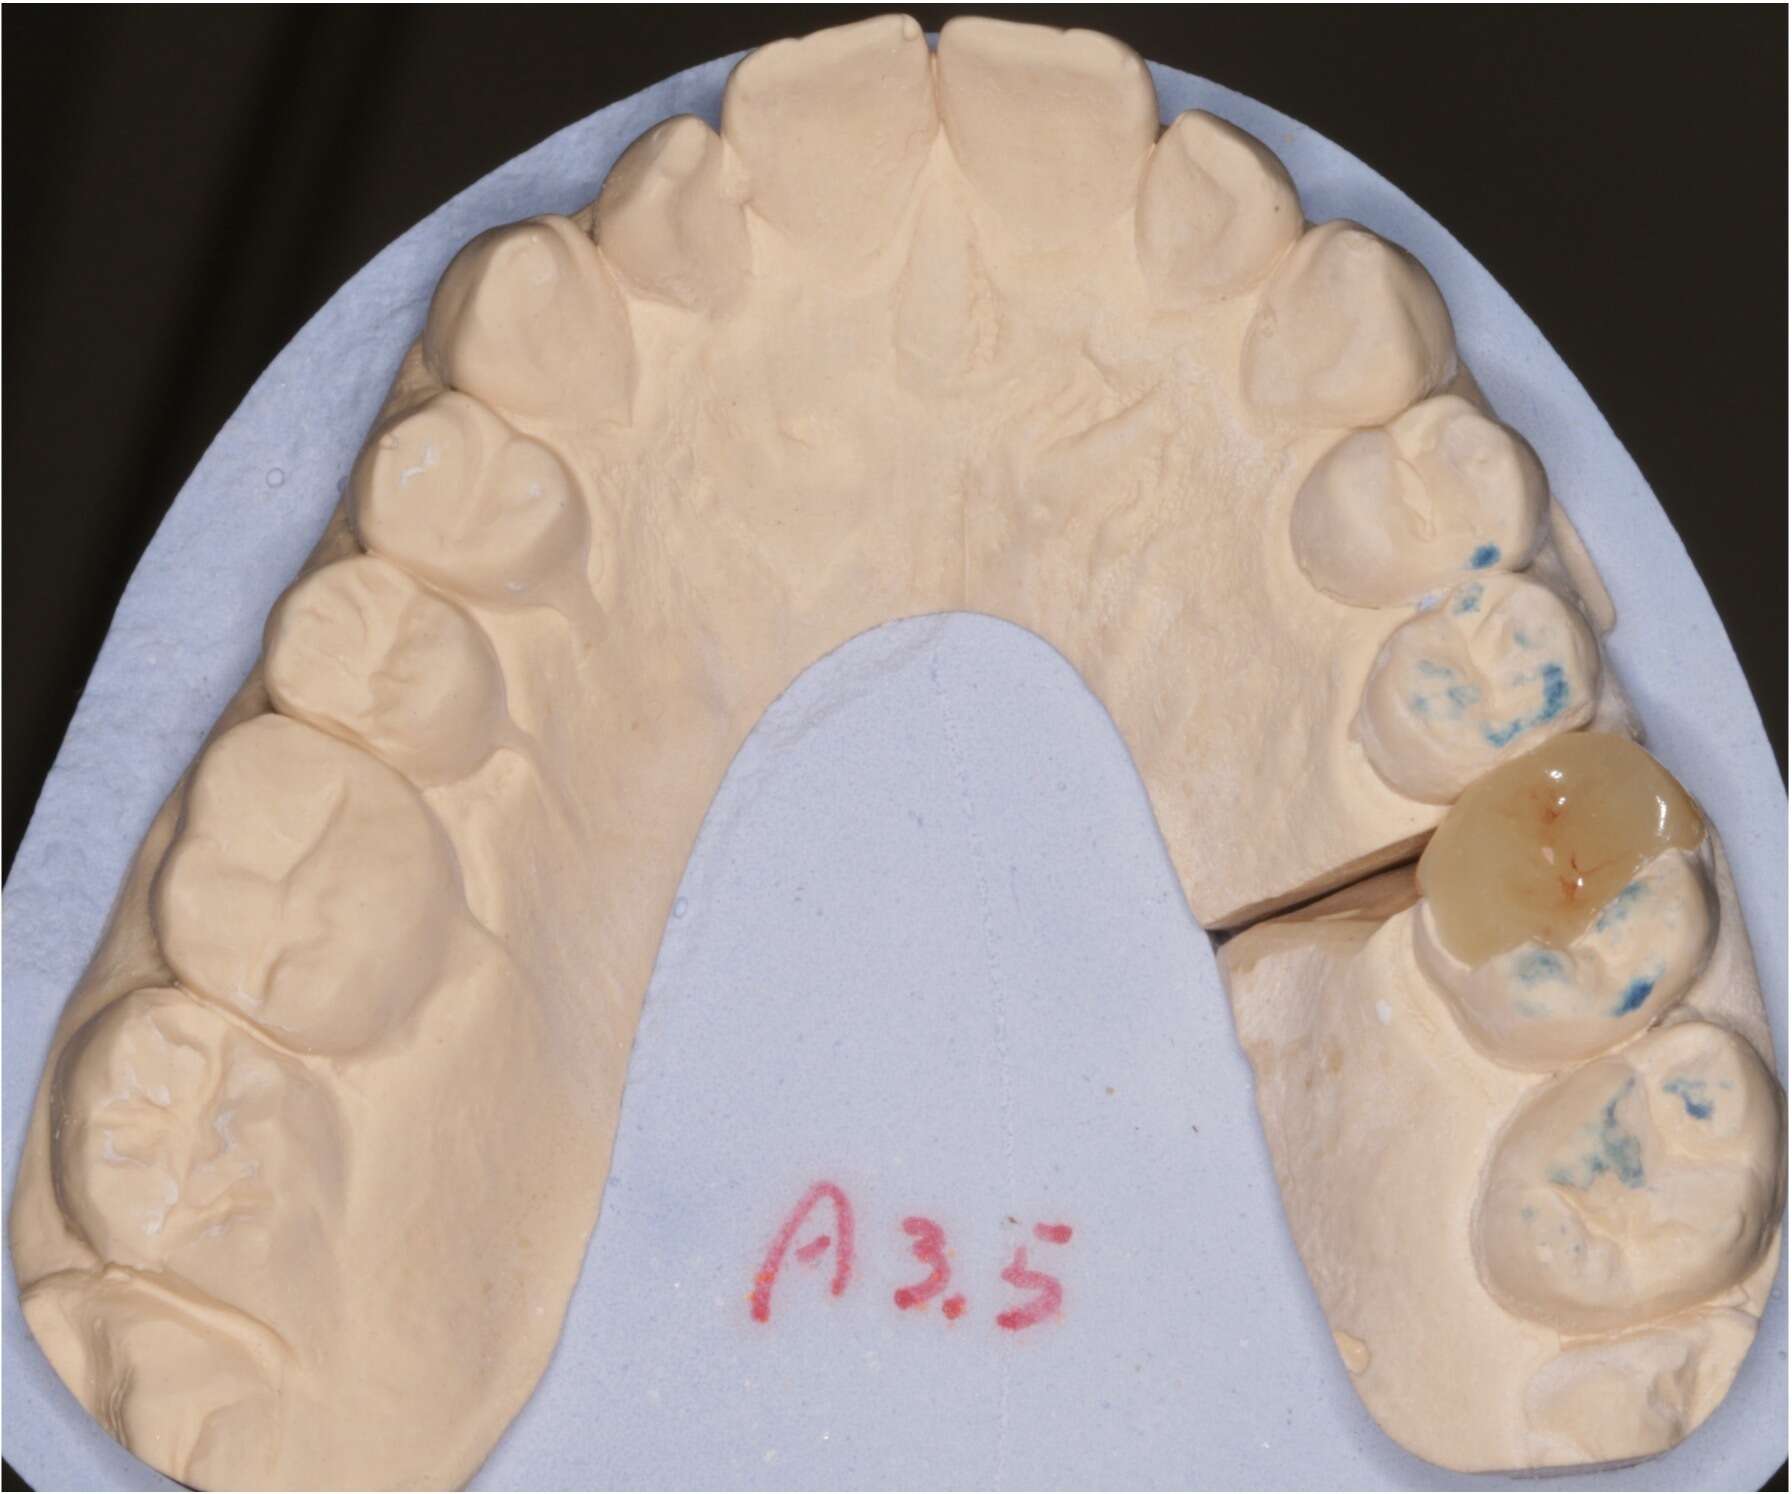

Réalisation d'un onlay en céramique par le laboratoire

Après essayage, le collage de L'onlay est réalisé.